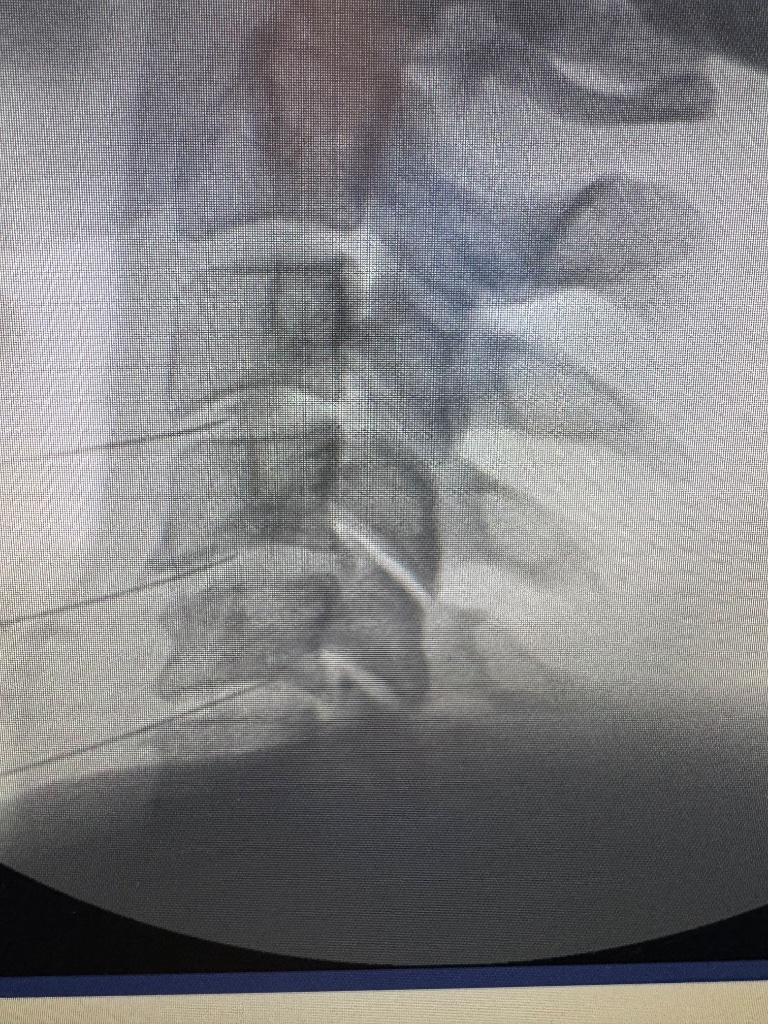

This is what happens when you stick needles in discs and F around with the nucleus. 1 year between these MRIs.

Who needs an acdf with this technique… saves recovery time and anesthesia risk!This is what happens when you stick needles in discs and F around with the nucleus. 1 year between these MRIs.View attachment 417309View attachment 417311

Did he get a C6-7 perc disc?This is what happens when you stick needles in discs and F around with the nucleus. 1 year between these MRIs.View attachment 417309View attachment 417311

Yes all the levels with worsened degeneration, ModicDid he get a C6-7 perc disc?

interesting screw...

I didn’t do that partinteresting screw...